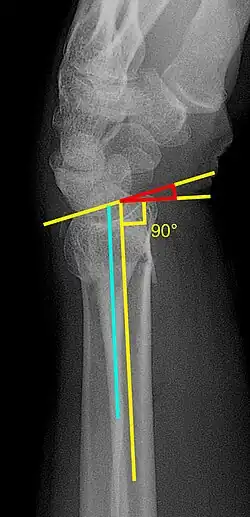

- Volar or dorsal tilt - A line is drawn joining the most distal ends of the volar and dorsal side of the radius. Another line perpendicular to the longitudinal axis of the radius is drawn. The angle between the two lines is the angle of volar or dorsal tilt of the wrist. Measurement of volar or dorsal tilt should be made in true lateral view of the wrist because pronation of the forearm reduces the volar tilt and supination increases it. When dorsal tilt is more than 11 degrees, it is associated with loss of grip strength and loss of wrist flexion.[4]

- Radial inclination - It is the angle between a line drawn from the radial styloid to the medial end of the articular surface of the radius and a line drawn perpendicular to the long axis of the radius. Loss of radial inclination is associated with loss of grip strength.[4]

- Radial length - It is the vertical distance in millimetres between a line tangential to the articular surface of the ulna and a tangential line drawn at the most distal point of radius (radial styloid). Shortening of radial length more than 4mm is associated with wrist pain.[4]

- Ulnar variance - It is the vertical distance between a horizontal line parallel to the articular surface of the radius and another horizontal line drawn parallel to the articular surface of the ulnar head. Positive ulnar variance (ulna appears longer than radius) disturbs the integrity of triangular fibrocartilage complex and is associated with loss of grip strength and wrist pain.[4]